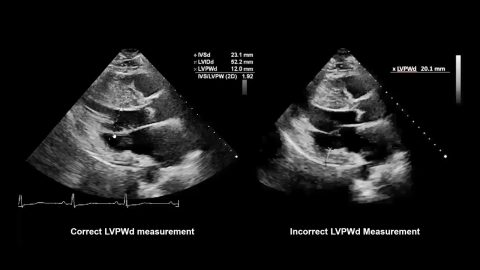

Thick Cardiac Wall

This video from ASE’s Microlesson Series on Hypertrophic Cardiomyopathy (HCM) answers the question, “In what disease states is the cardiac wall thickened?”